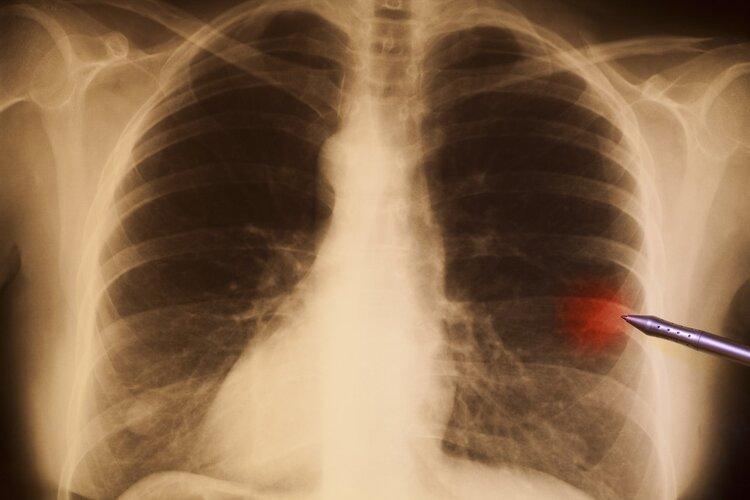

“醫生,我不煙不酒,爲什麼患肺癌的偏偏是我!”平常自認爲生活習慣很好的劉女士,怎麼也沒想到自己才43歲,就被肺癌盯上!

原來近段時間以來,劉女士總是胸痛、咯血,實在難以忍受便到了醫院就診,結果被癌症肺癌。這讓煙酒不沾的她一時無法接受,擔心是誤診,醫生解釋劉女士的肺癌可能與被動吸入二手菸、長期情緒不佳等因素有關。

其實,吸菸和不吸菸患上的肺癌類型並不一樣。福建省腫瘤醫院腫瘤內科主任醫師林根介紹:肺癌可以分爲小細胞肺癌非小細胞肺癌兩類,其中非小細胞肺癌在肺癌中佔比75%—85%。90%的小細胞癌患者是菸民,肺腺癌患者中不吸菸的人很多,而且近三十年來女性肺癌患者越來越多。